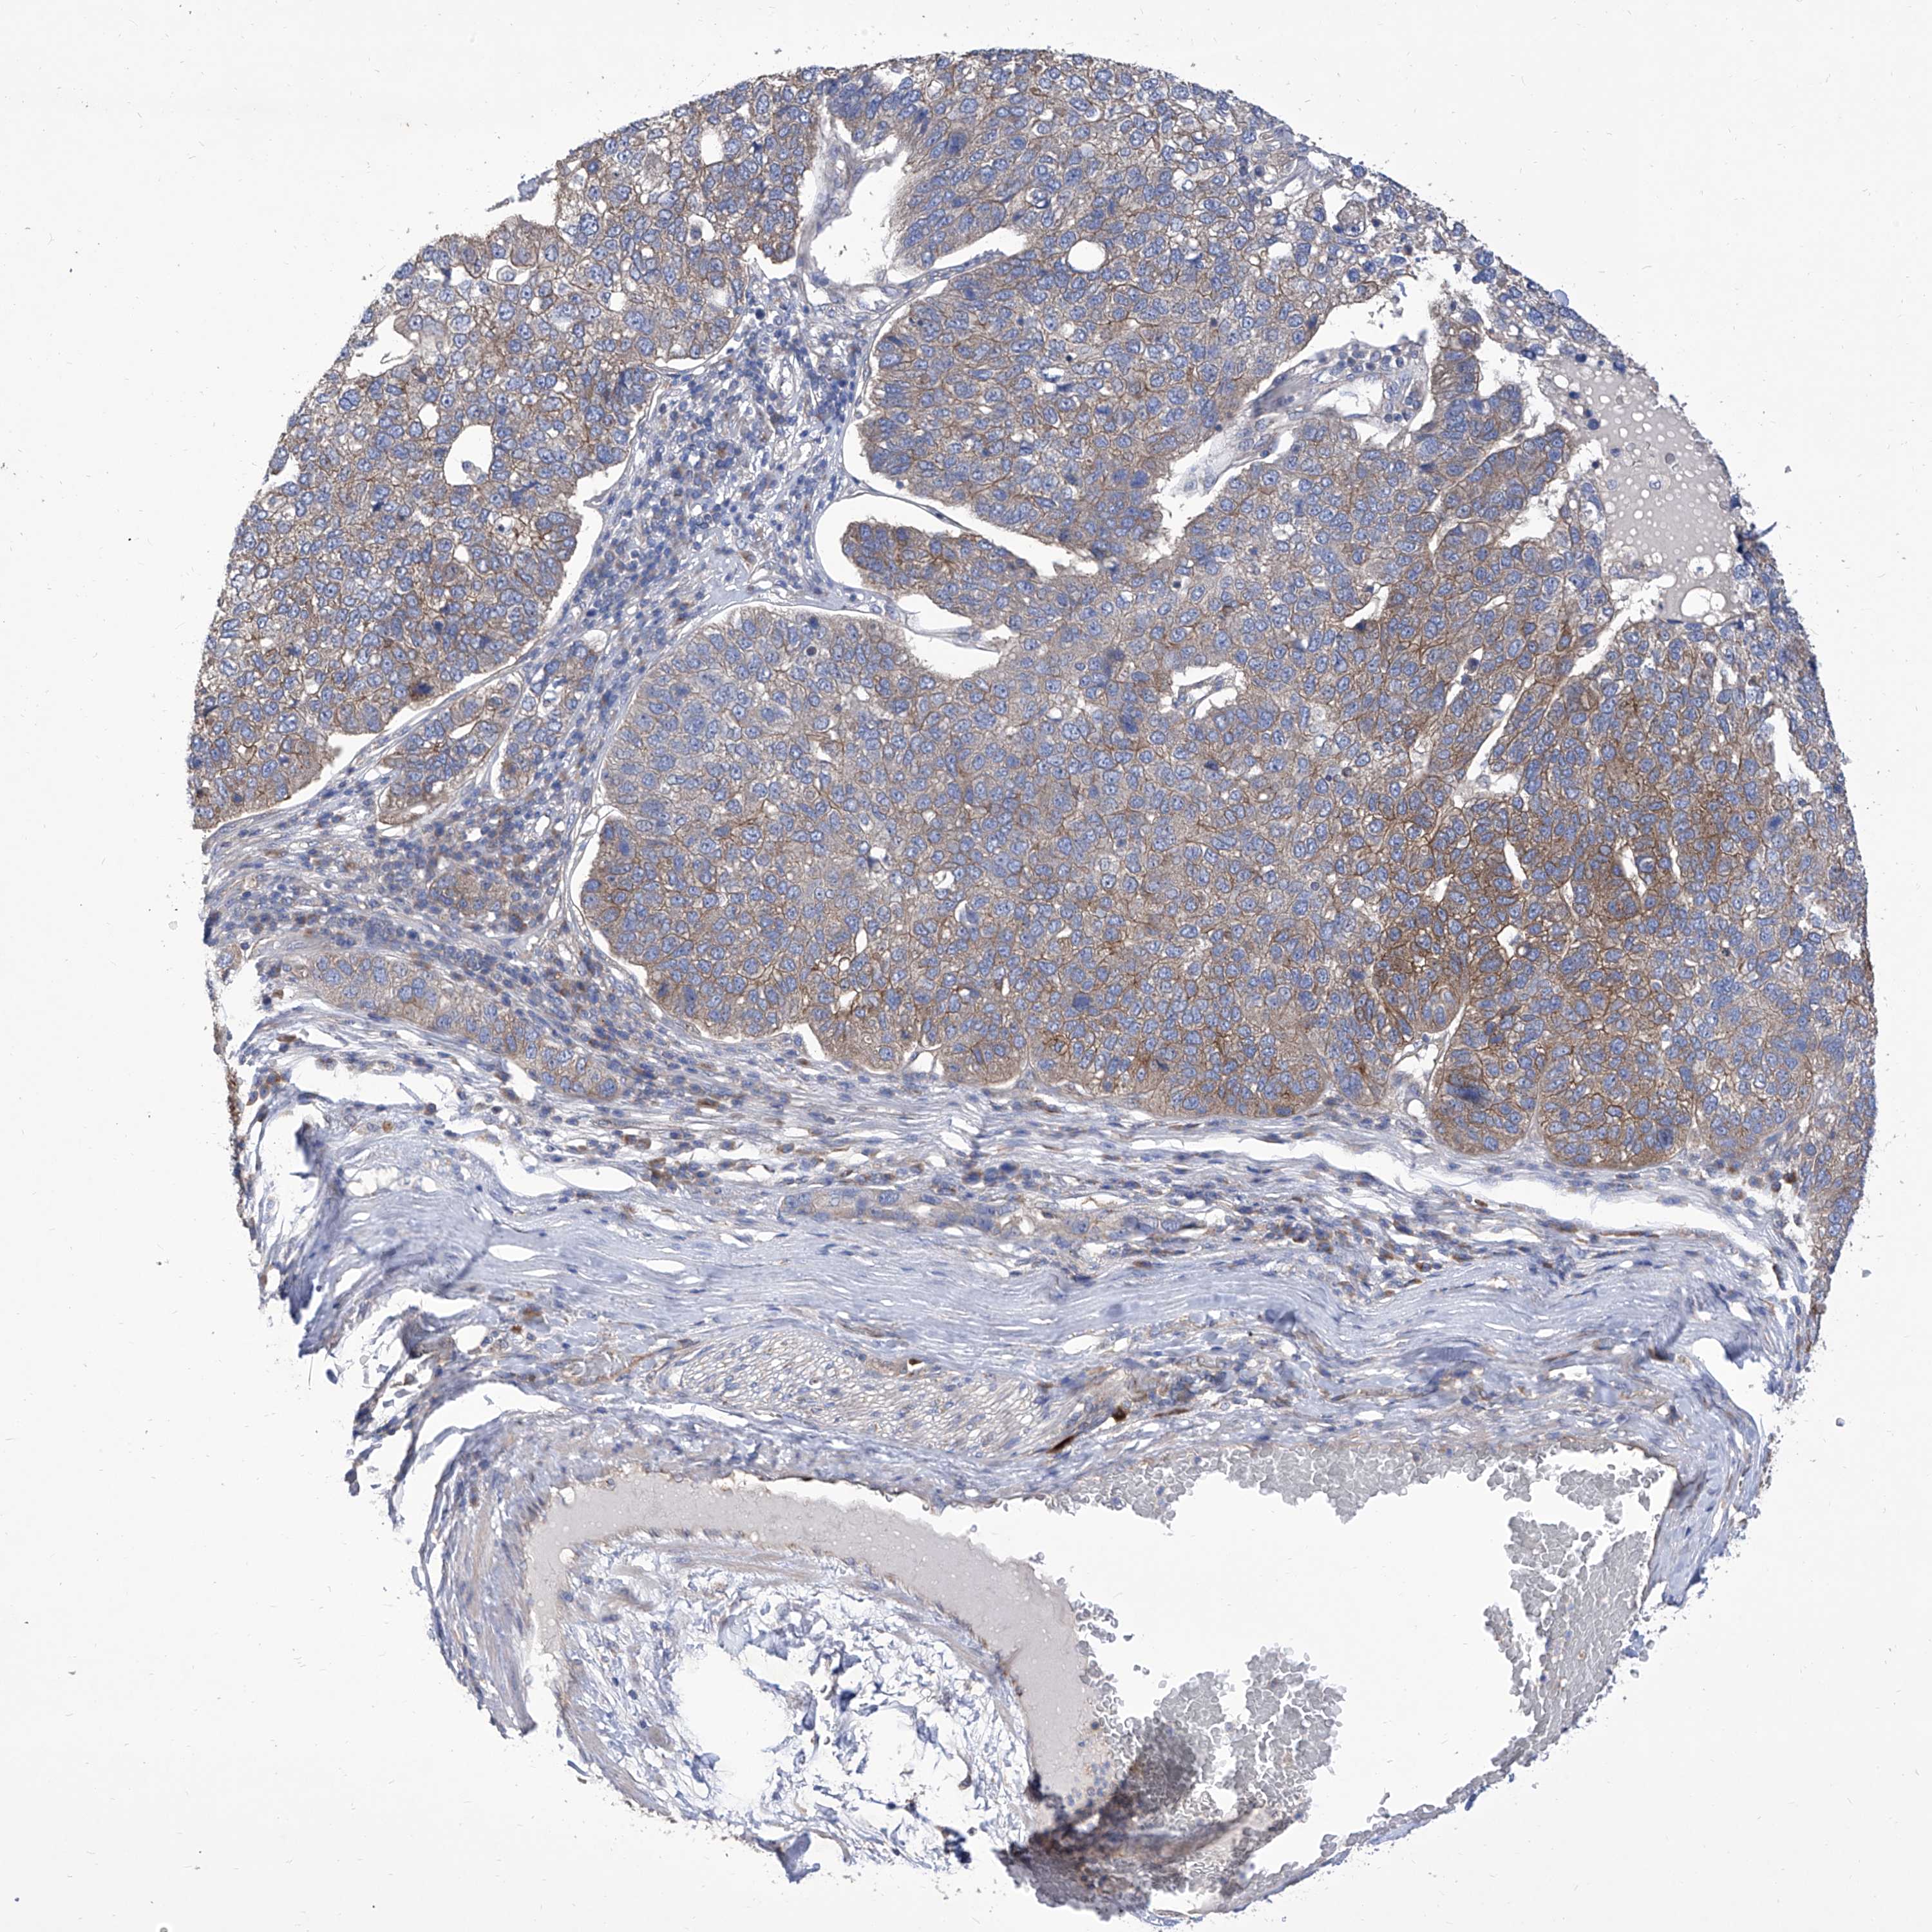

PANCREATIC CANCER - Protein expressioni

A mouse-over function shows sample information and annotation data. Click on an image to view it in a full screen mode. Samples can be filtered based on level of antibody staining by selecting one or several of the following categories: high, medium, low and not detected. The assay and annotation is described here.

Note that samples used for immunohistochemistry by the Human Protein Atlas do not correspond to samples in the TCGA dataset.

Antibody stainingi

Antibody staining in the annotated cell types in the current human tissue is reported as not detected, low, medium, or high, based on conventional immunohistochemistry profiling in selected tissues. This score is based on the combination of the staining intensity and fraction of stained cells.

Each image is clickable and will lead to virtual microscopy that enables deeper exploration of all samples and also displays staining intensity scores, fraction scores and subcellular localization as well as patient and tissue information for each sample.

Antibody HPA030164

Antibody HPA030165

Antibody HPA030166

Staining

High

Medium

Low

Not detected

Intensity

Strong

Moderate

Weak

Negative

Quantity

>75%

75%-25%

<25%

None

Location

Nuclear

Cytoplasmic/membranous

Cytoplasmic/membranous,nuclear

Adenocarcinoma, NOS